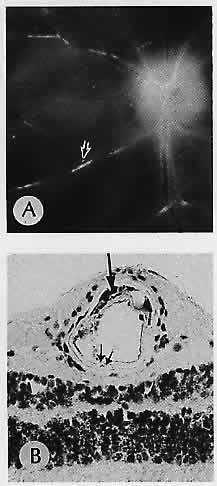

GROUPED PIGMENTATION (Fig. 1)

Fig. 1. Grouped pigmentation. A. Macroscopic appearance of pigmented plaques. Inset. Fundus shows a typical grouped pigmentation. B. Flat preparation of retinal pigment epithelium (RPE) showing a greater concentration of pigment granules in cells corresponding to grouped pigmentation. C. RPE in a normal area adjacent to the plaque. D. RPE in the area of the plaque shows a greater concentration of pigment granules. The overlying retina is detached artifactitiously. (A, macroscopic; inset, fundus; B, flat preparation, H&E, ×256; C, H&E, ×640; D, H&E, ×640)

The sensory retina is transparent. Pigmentation seen through it reflects underlying pigment from the retinal pigment epithelium or choroid. The hyperpigmentation of grouped pigmentation results from retinal pigment epithelial cells that are larger and contain more pigment granules than normal. The granules are large and spherical, and the cell density is higher than normal.7 Sometimes the grouped pigmentation resembles the footprints of an animal, hence the picturesque name “bear tracks.” The condition is benign and stationary. The area of retinal pigment epithelial hypertrophy may also be large and solitary, but the histology is identical to the grouped type. Lacunae of depigmentation may occur focally or diffusely.7

This phenomenon is generally harmless and of little clinical consequence. An exception is Gardeners syndrome, which is one form of hereditary gastrointestinal polyposis with nongastrointestinal manifestations, including benign soft tissue tumors, osteomas, and bilateral congenital retinal pigment epithelial hypertrophy.8 Another such syndrome is Turcot syndrome, which includes adenomatous polyps, hypertrophic pigment epithelium, and epithelial tumors of the central nervous syndrome. All may be part of a spectrum.9 The gastrointestinal polyps are adenomatous and thus have malignant potential. Because the retinal pigment epithelial hypertrophy is congenital, ophthalmic examination is potentially lifesaving in identifying persons at risk for these autosomally inherited conditions.10